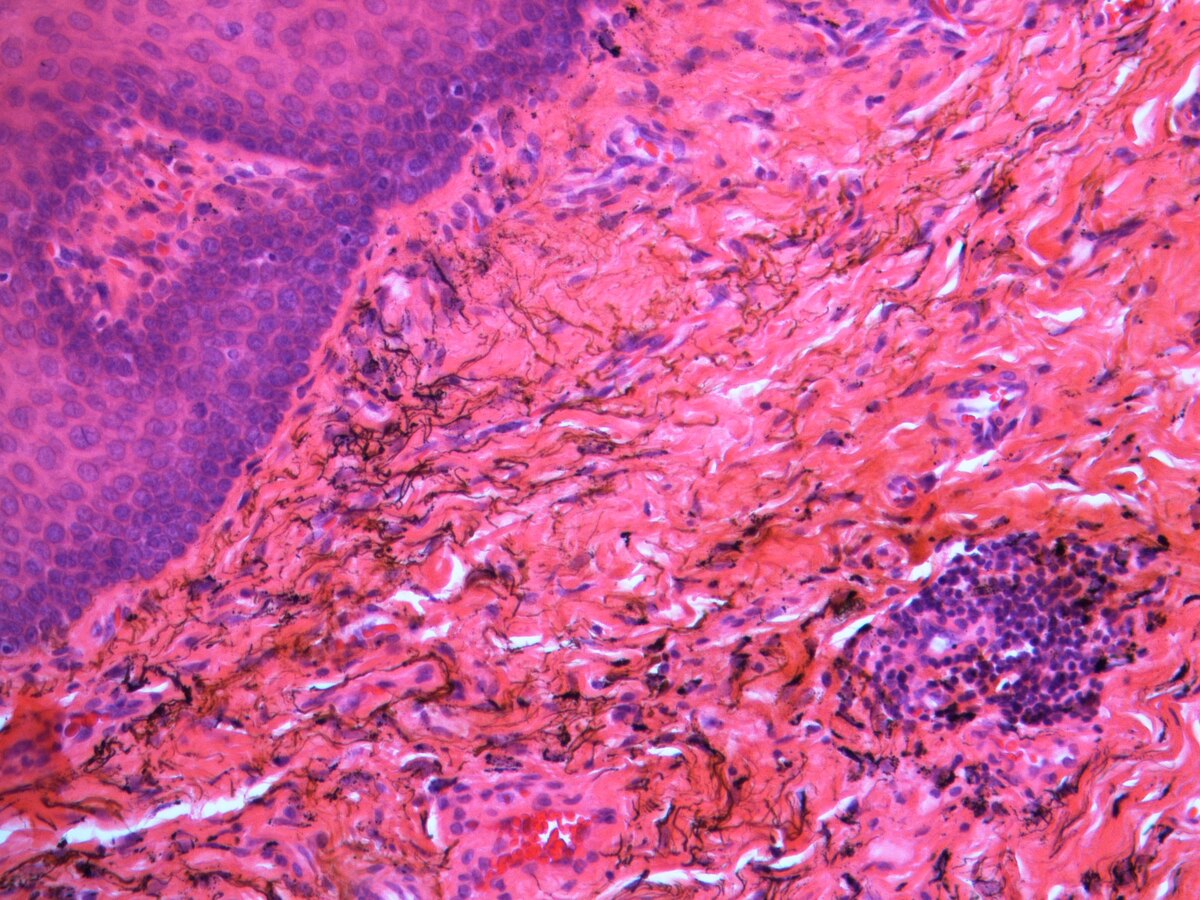

One of the most common causes of "black gum disease" is actually Subgingival Calculus. We all know plaque is that sticky yellow film on our teeth. But when plaque isn't removed, it hardens into tartar (calculus).

According to Wikipedia's entry on Dental Calculus, when this tartar forms below the gumline, it can absorb pigments from blood and other fluids, turning it black or dark brown. Because the gum tissue over it is translucent, this dark calculus shows through, creating the appearance of a black gumline.